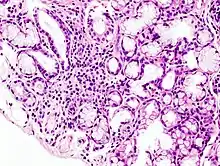

While the exact cause is unclear, it is believed to involve a combination of genetics and an environmental trigger such as exposure to a virus or bacteria.[5] It can occur independently of other health problems (primary Sjögren syndrome) or as a result of another connective tissue disorder (secondary Sjögren syndrome).[4] The inflammation that results progressively damages the glands.[8] Diagnosis is by biopsy of moisture-producing glands and blood tests looking for specific antibodies.[3] On biopsy there are typically lymphocytes within the glands.[3]

A lip/salivary gland biopsy takes a tissue sample that can reveal lymphocytes clustered around salivary glands, and damage to these glands from inflammation. This test involves removing a sample of tissue from a person’s inner lip/salivary gland and examining it under a microscope. In addition, a sialogram, a special X-ray test, is performed to see if any blockage is present in the salivary gland ducts (i.e. parotid duct) and the amount of saliva that flows into the mouth.[41]

A radiological procedure is available as a reliable and accurate test for SS. A contrast agent is injected into the parotid duct, which opens from the cheek into the vestibule of the mouth opposite the neck of the upper second molar tooth. Histopathology studies should show focal lymphocytic sialadenitis. Objective evidence of salivary gland involvement is tested through ultrasound examinations, the level of unstimulated whole salivary flow, a parotid sialography or salivary scintigraphy, and autoantibodies against Ro (SSA) and/or La (SSB) antigens.

History